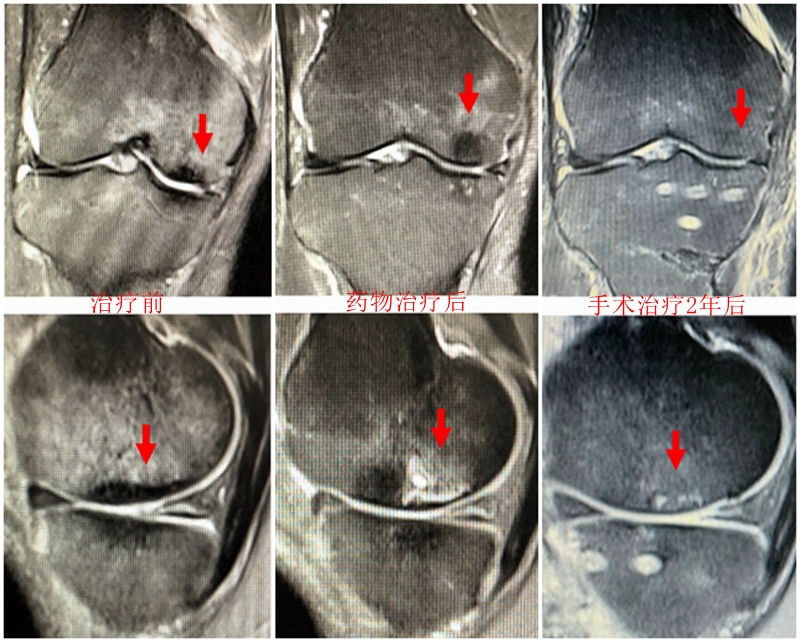

病例1:女,61岁,右膝关节诊断为Koshino Ⅲ期SONK,行右膝内侧单髁手术治疗。

病例1:男,64岁,主诉左膝关节内侧疼痛6年余。MR提示骨坏死区占比为33.28%,矢状位病变区域前后径为26.42mm,半月板相对突出百分比(RPE)31.78%,同时存在胫骨侧来源的下肢内翻畸形(MPTA83°),关节线会聚角2°。

行关节镜检查+软骨摘除+微骨折+HTO术,术后随访2年恢复良好,活动自如,行走时无左膝关节疼痛不适。